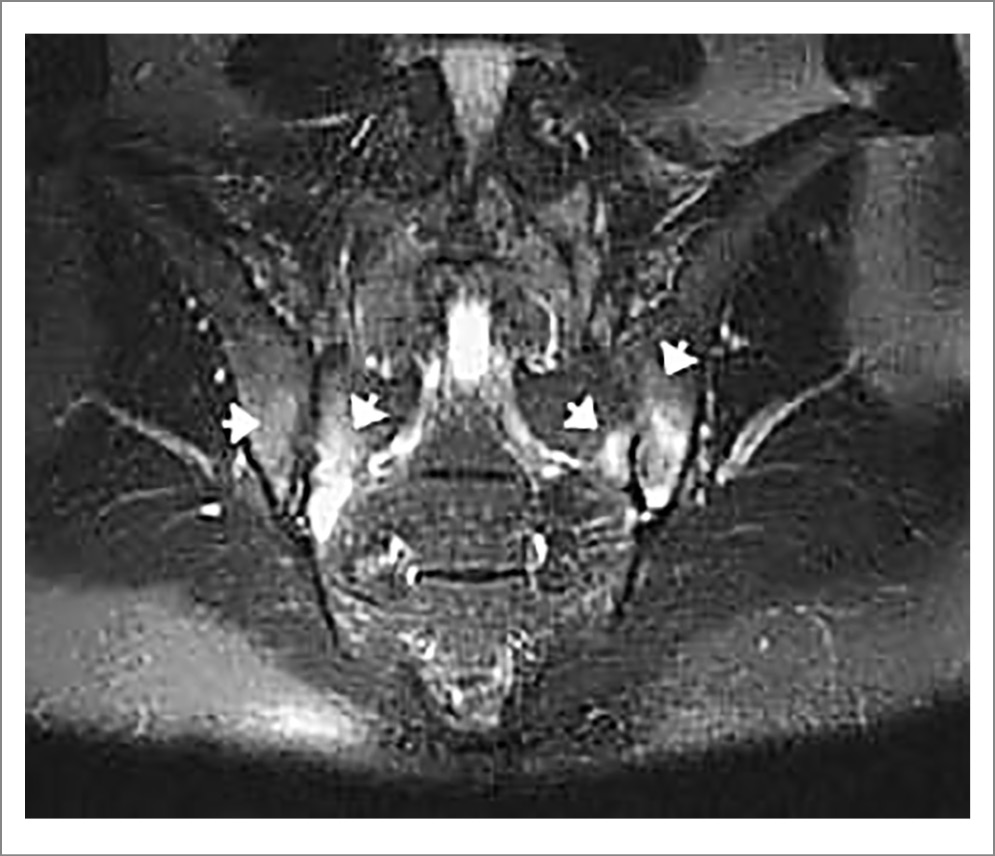

Рис. 10. Пациент Б., диагноз АС. МРТ КПС (коронарная проекция, режим Т2 FatSat): множественные зоны отека костного мозга (указаны стрелками) в основном в субхондральных областях. Изменения соответствуют критериям «активного» сакроилиита по классификации ASAS [22].